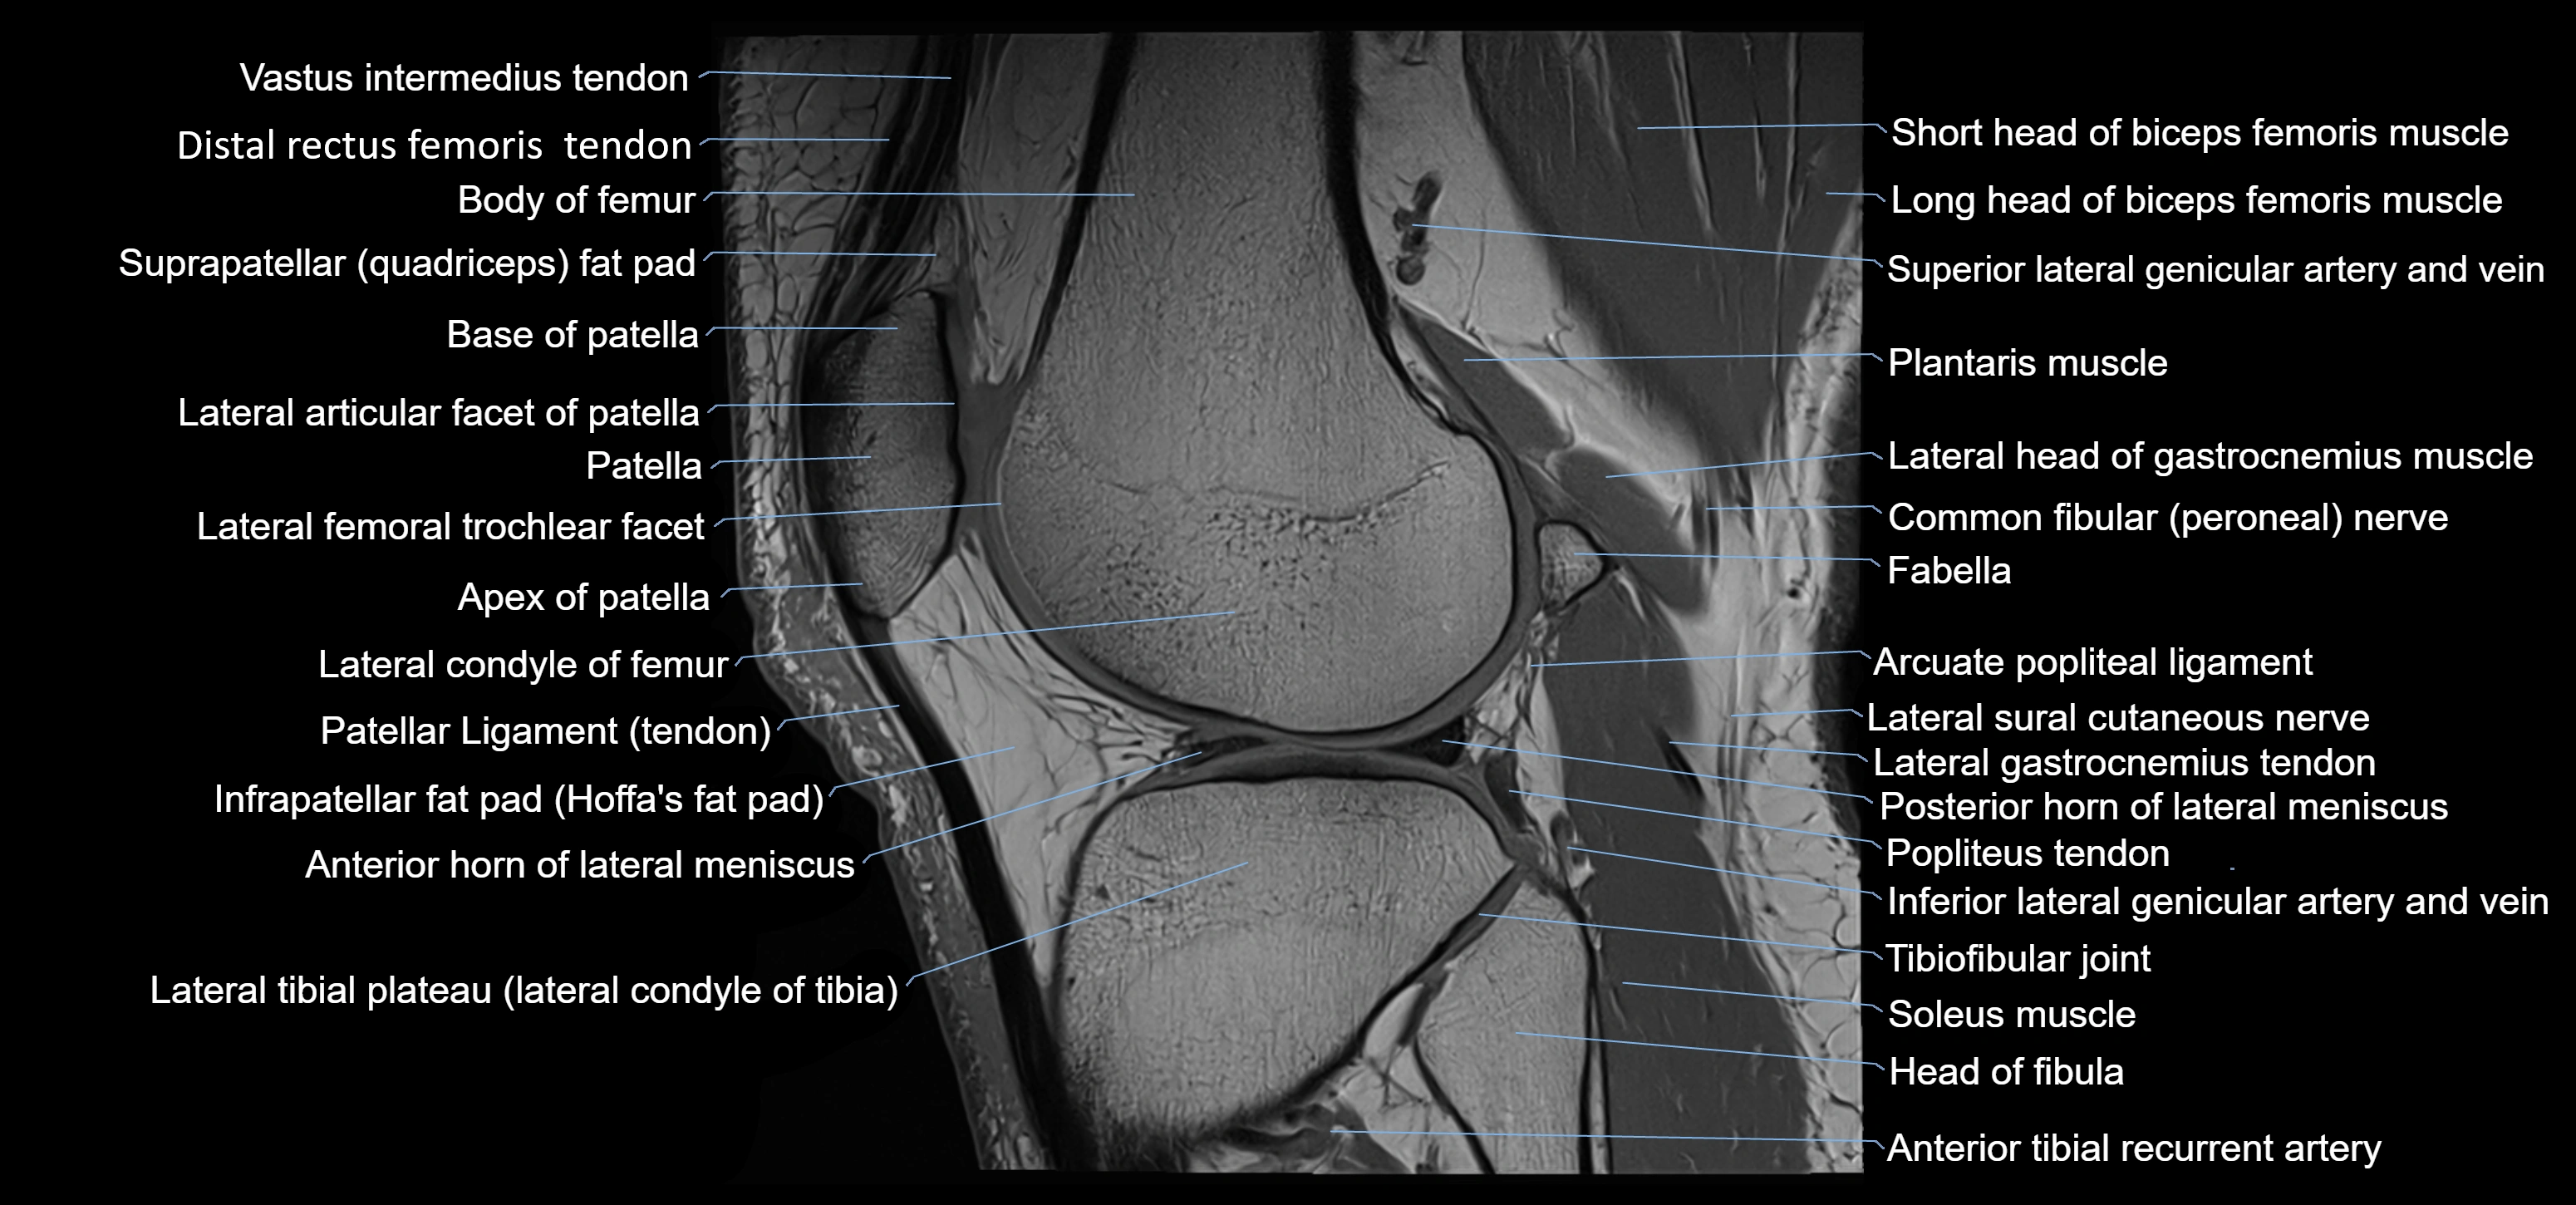

- Anterior horn of lateral meniscus

- Apex of patella

- Base of patella

- Body of femur

- Distal rectus femoris tendon

- Distal vastus intermedius tendon

- Head of fibula

- Infrapatellar fat pad

- Lateral articular facet of patella

- Lateral condyle of femur

- Lateral gastrocnemius tendon

- Lateral head of gastrocnemius muscle

- Lateral meniscus

- Lateral tibial plateau

- Neck of fibula

- Patella

- Patellar tendon (patellar ligament)

- Plantaris muscle

- Popliteus tendon

- Posterior horn of lateral meniscus

- Prefemoral fat pad

- Soleus muscle

- Superior lateral genicular artery

- Superior lateral genicular vein

- Superior tibiofibular joint

- Suprapatellar fat pad

- Tibiofibular joint (proximal)

- Vastus lateralis muscle